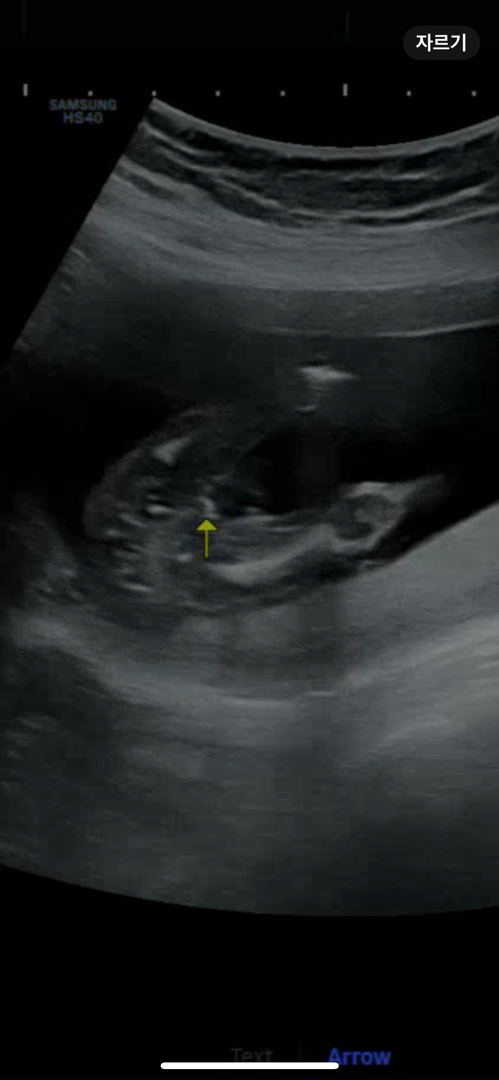

18주입니다~!성별 봐주세용

원장님께서는 잘 모르겠다며 딸일거 같다고는 하셨는데ㅠㅠ 딸일까요 아들일까용...?🥹

고추로 안보이는데요? 고추로 보이시면 뾰족한게 많이 튀어나와야되요~